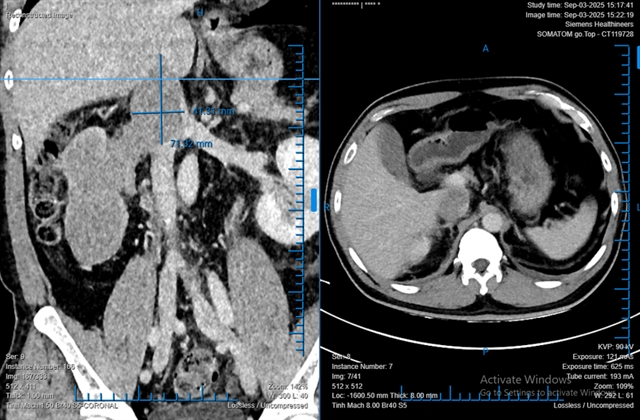

호치민시 빈단(Bình Dân)병원에서 로봇 전용 수술로 신장 전체를 차지한 68×86×138mm 크기의 종양과 하대정맥으로 76mm 연장된 종양혈전을 완전히 제거했다.

호치민시 빈단(Bình Dân)병원 의료진이 로봇만으로 신장 전체를 차지한 대형 종양과 하대정맥으로 76mm 뻗은 종양혈전을 성공적으로 제거했다.